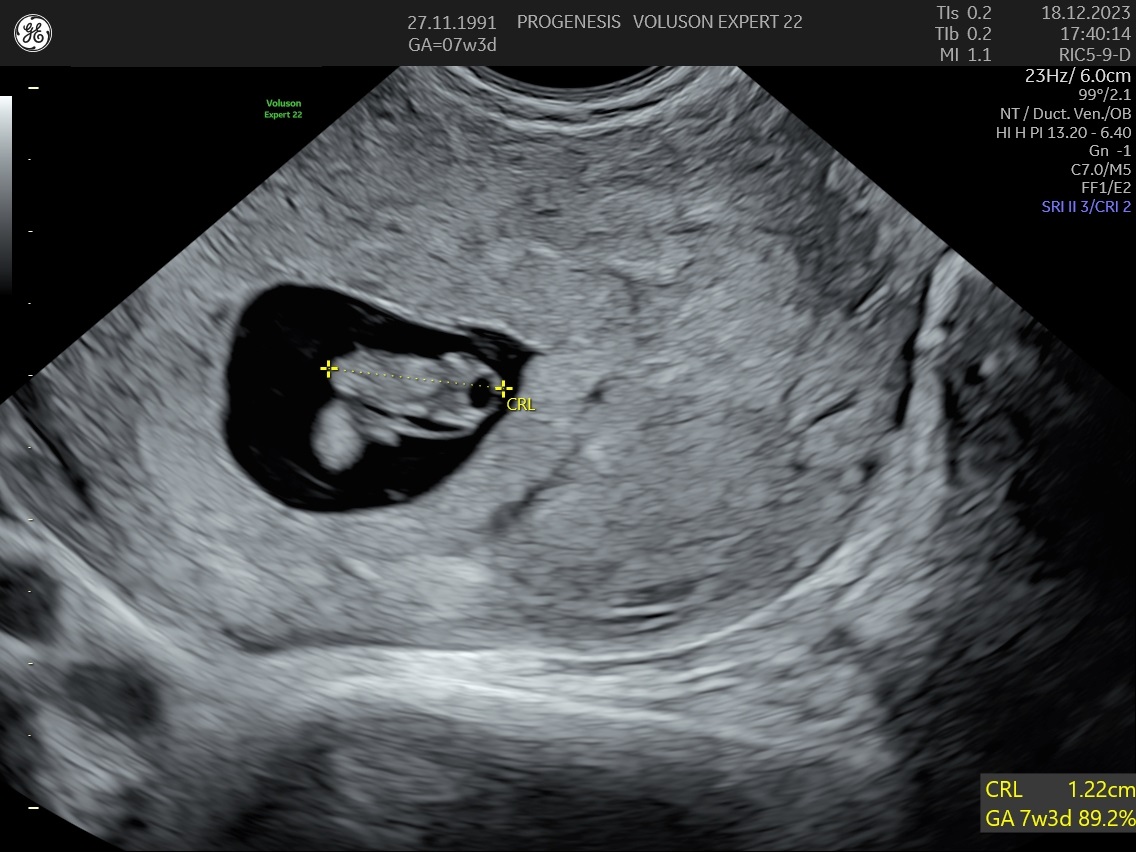

Υπερηχογράφημα Αρχόμενης Κύησης

(6-11 εβδομάδων)

Σκοπός της εξέτασης είναι να επιβεβαιώσουμε ότι υπάρχει φυσιολογικά εξελισσόμενη κύηση μέσα στη μήτρα, αναγνωρίζοντας έμβρυο με καρδιακή λειτουργία, και  αποκλείοντας την εξωμήτριο  κύηση.

Επιπλέον, αναγνωρίζεται ο αριθμός των εμβρύων, έχουμε μία πρώτη εκτίμηση της ηλικίας κύησης καθώς και της χοριονικότητας (εάν δηλαδή τα έμβρυα μοιράζονται τον ίδιο πλακούντα) στη περίπτωση της πολύδυμης κύησης.